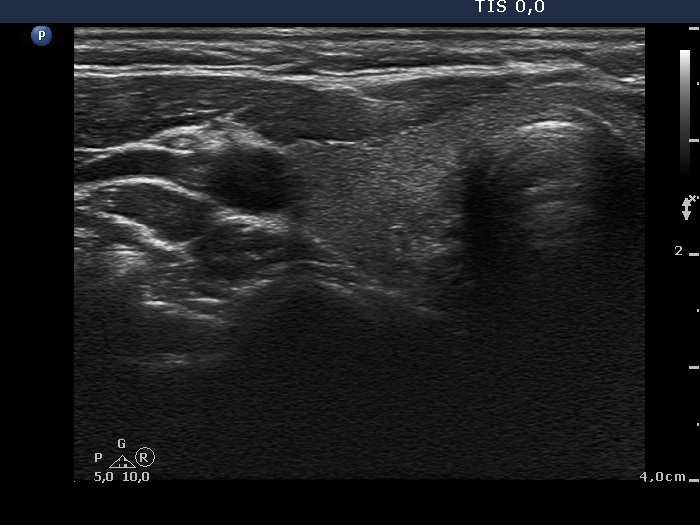

First examination (first and second row of images):

Clinical presentation: A 33-year-old woman was referred with typical complaints of subacute thyroiditis lasting for 6 weeks.

Palpation: Both lobes were hard and painful.

Functional state: moderate degree of hyperthyroidism with TSH-level 0.001 mIU/L, FT4 27.2 pM/L. Erythrocyte sedimentation rate was 49 mm/H, CRP was 9.2 mg/L.

Ultrasonography: The thyroid was hypoechogenic and inhomogeneous. The vascularization was average.

Cytological diagnosis: subacute, granulomatous de Quervain's thyroiditis.

Suggestion: steroid therapy for 6 weeks.